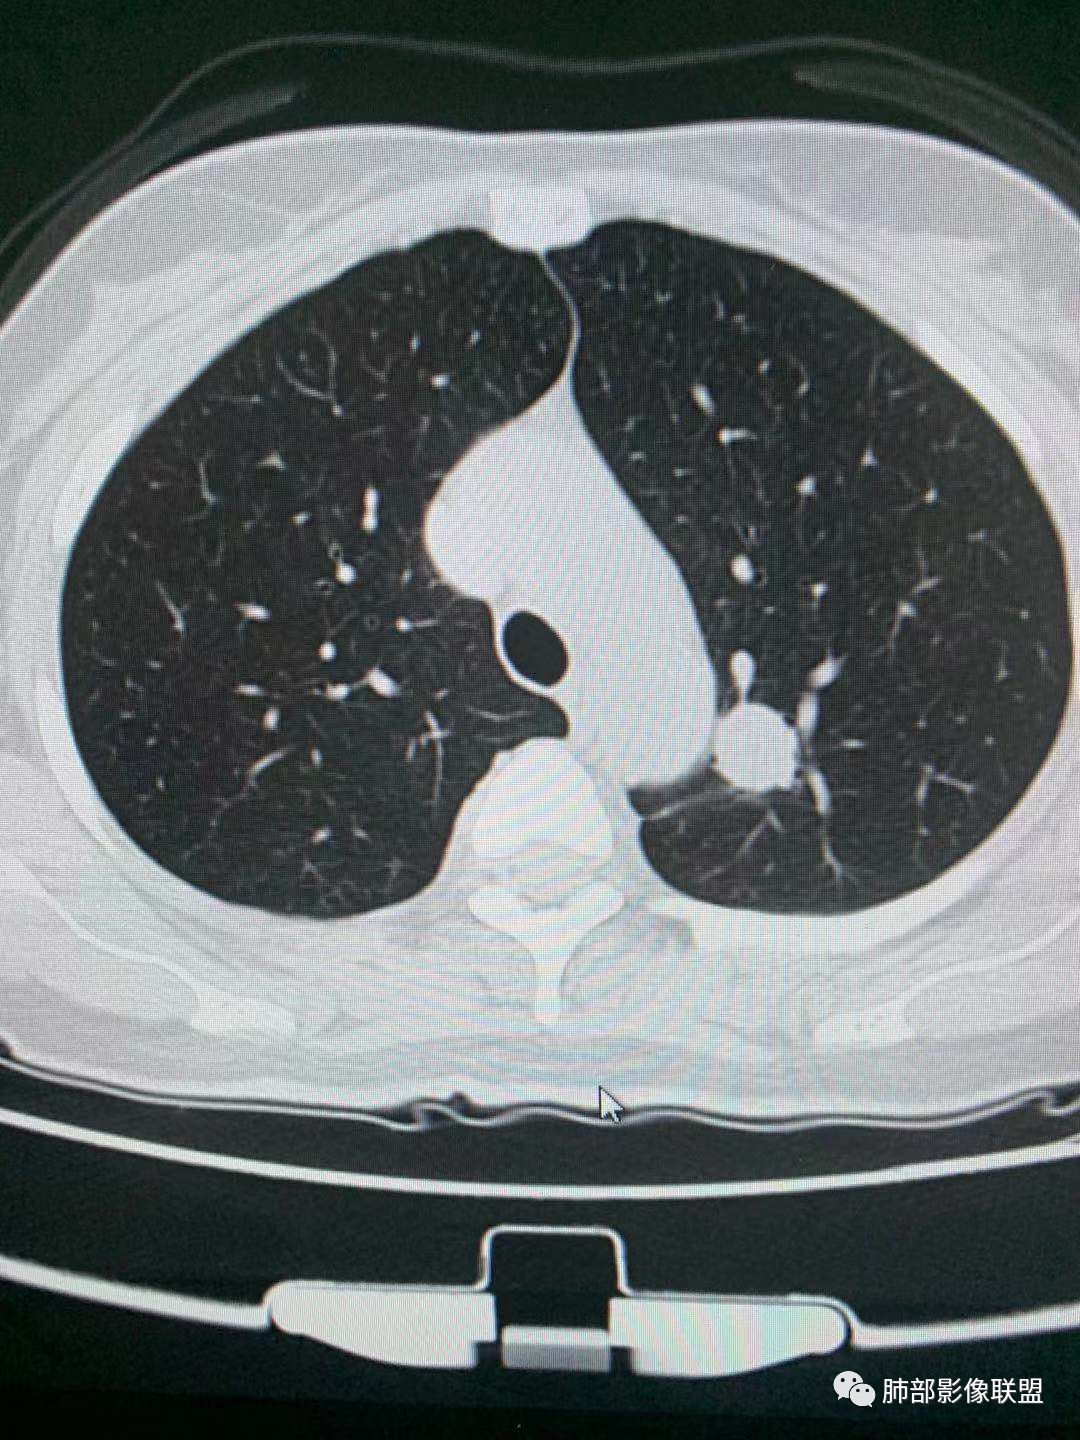

左肺上叶实性结节,光滑,支气管血管贴边,晕,强化持续。两年前就有,考虑psp。另外左肺上叶纵膈侧胸膜下及中带两处混合磨玻璃结节,考虑原位和微浸润可能,需要随访看看。

左肺上叶实性结节,边缘光滑清晰,血管贴边,渐进性延迟强化,密度均匀,考虑PSP. 医学百科网 | YxBaike.Com

贴边血管征,强化延迟,考虑PSP 医学百科网 | YxBaike.Com

左肺上叶实性结节,边缘光滑清晰,血管贴边,渐进性延迟强化,密度均匀,考虑PSP.但是强化幅度不够,需要鉴别早期肺癌

最大的靠后,有血管贴边征,渐进性明显强化,考虑PSP可能大

靠前部中等大小结节考虑MIA

靠中部最小的那个结节AAH或者慢性炎症均有可能 医学百科网 | YxBaike.Com

中年女性,左肺上叶实性圆形结节,边缘有晕,血管及支气管贴边,强化尚均匀,渐进性明显强化,考虑为PSP可能 医学百科网 | YxBaike.Com